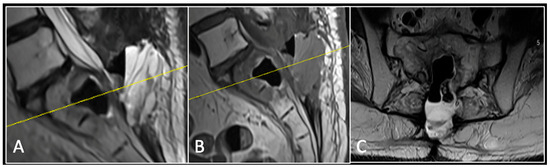

2.2. Case 2: Sacral Chordoma

This 63-year-old male presented with sacral pain and right-sided S1 radiculopathy. He was subsequently referred to our institution after diagnostic imaging revealed a destructive lesion within the S1 vertebra (Figure 4). The patient developed symptoms of acute cauda equina syndrome, for which we recommended an emergent surgical decompression to be performed at the referring hospital. Biopsy confirmed a conventional chordoma. The patient chose to undergo separation surgery, given the significant morbidity associated with an en-bloc sacral resection, including sacrifice of the neural structures innervating his bladder and bowel. He received adjuvant proton beam therapy, and 6-monthly surveillance imaging revealed stable disease (Figure 5). Unfortunately, 12 months post-separation surgery, there was evidence of tumour progression with epidural extension and symptomatic deterioration in bladder function, requiring revision surgical debulking (Figure 6).

Figure 4.

MRI demonstrating a destructive lobular sacral mass (arrow) with invasion of the S1 vertebral body and complete compression of the cauda equina neural elements. The yellow line on the axial image represents the plane of the corresponding axial section. (A) T2W sagittal; (B) T1W sagittal; (C) T2W axial.

Figure 5.

MRI imaging following separation surgery. (A) T2W sagittal; (B) T1W sagittal; (C) T2W axial. Imaging shows removal of posterior lumbosacral elements with residual disease (arrow) within the S1 vertebral body but significant reduction in tumour dimensions. The yellow line on the sagittal images indicates the level at which the axial image was obtained.

Figure 6.

MRI imaging following revision debulking surgery. (A) T2W sagittal; (B) T1W sagittal; (C) T2-weighted axial. Imaging shows an air cavity within the S1 vertebral body where tumour has been resected and fluid within the epidural space that is displacing the thecal sac posteriorly. The yellow line on the sagittal images denotes the level corresponding to the axial section.